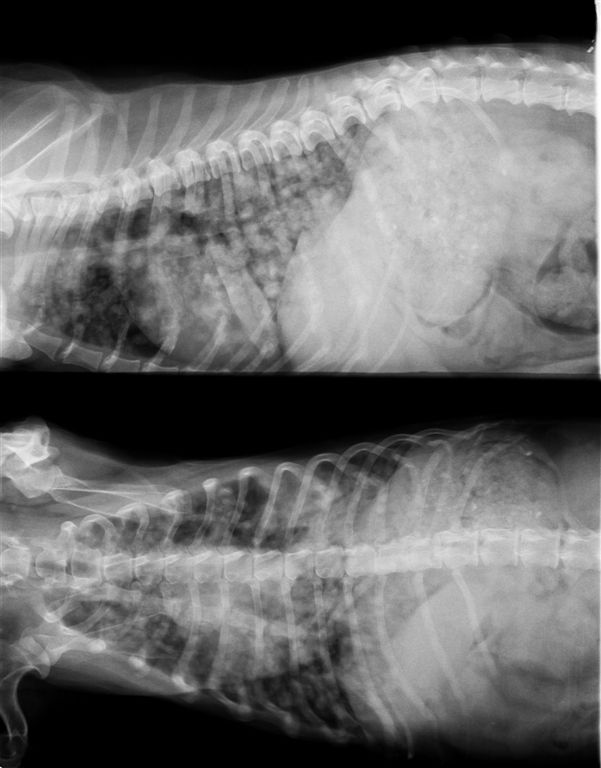

犬 13歳 乳腺腫瘍

肺にびまん性転移像がみられる。1年前に乳腺腫瘍の手術をうけ右側乳腺を切除したが、左側乳腺をそのままにしたため、拡大し現在腫瘍は8cmを超える。このような場合は手術などで体調が崩れると悪化が加速する場合が多い。